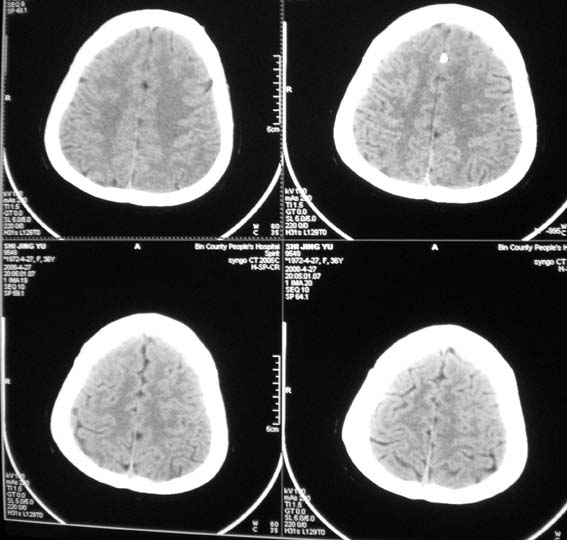

标题: CT13124:女,36岁,常短暂性意识丧失。 [打印本页]

女,36岁,常短暂性意识丧失。

颅脑ct平扫未见明显异常。

右顶部放射冠部白质内异常灰质团块影 考虑灰质移位症可能

患者短暂性意识丧失考虑为癫痫小发作

鞍上池右侧旁脑质内见团块稍高密度影,建议mr检查。